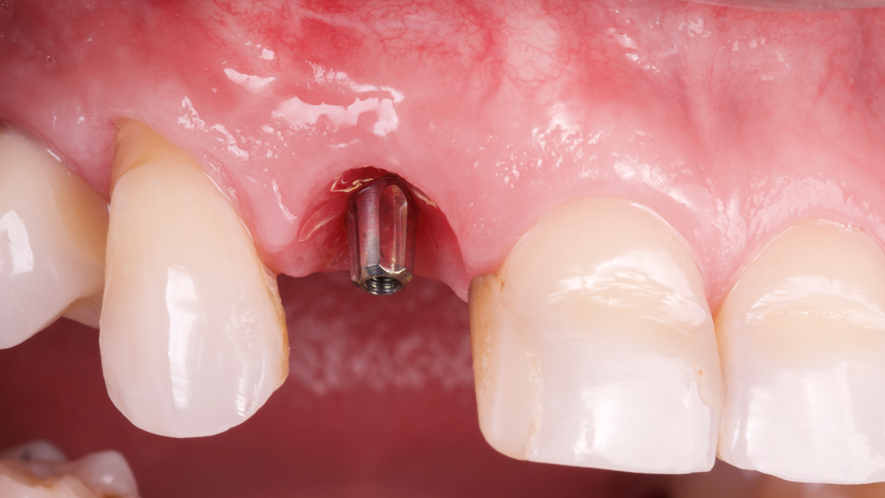

Este trabalho tem como objetivo relatar um caso clínico de exodontia minimamente invasiva de um incisivo lateral superior com fratura radicular, realizando implante imediato em alvéolo pós-extração, enxerto de tecido conjuntivo subepitelial e osso bovino liofilizado para preenchimento de GAP, prontamente à instalação de pilar reto e provisório imediato.